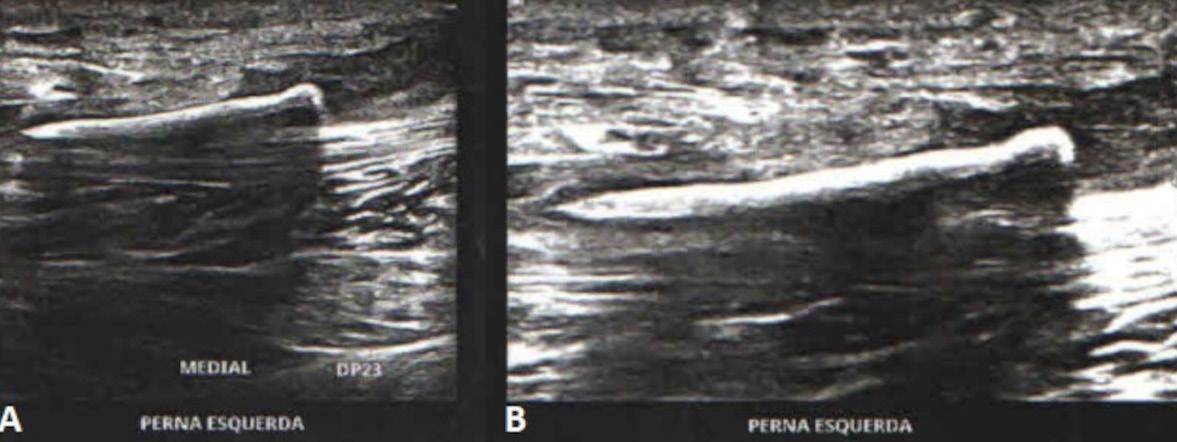

Relato de caso: a importância da transiluminação ungueal no diagnóstico e avaliação topográfica do tumor glômico subungueal

Micaelly Samara Meneses Santos, José Roberto Pegas, Raissa Piagentini de Andrade, Leonardo Silva Grassi, Vanessa Cristina Coimbra, Bianca Sousa de Almeida Neves